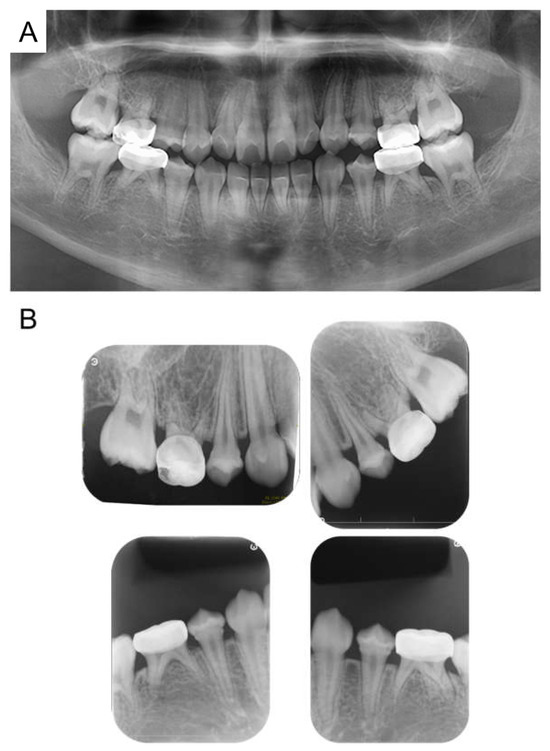

| Tooth | Diagnosis | Final Restoration |

|---|---|---|

| Maxilla | ||

| 51 | C2 | Resin-based composite crown |

| 52 | C2 | Resin-based composite crown |

| 53 | C2 | Resin filling |

| 54 | C2 | Preformed stainless-steel crown |

| 55 | C2 | Preformed stainless-steel crown |

| 61 | C2 | Resin-based composite crown |

| 62 | C2 | Resin-based composite crown |

| 63 | C2 | Resin filling |

| 64 | C2 | Preformed stainless-steel crown |

| 65 | C2 | Preformed stainless-steel crown |

| Mandible | ||

| 71 | C2 | No treatment |

| 72 | C2 | Resin filling |

| 73 | C2 | Resin filling |

| 74 | C2 | Preformed stainless-steel crown |

| 75 | C2 | Preformed stainless-steel crown |

| 81 | C2 | No treatment |

| 82 | C2 | Resin filling |

| 83 | C2 | Resin filling |

| 84 | C2 | Preformed stainless-steel crown |

| 85 | C2 | Preformed stainless-steel crown |